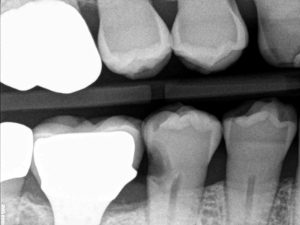

عکس1: پوسیدگیهای گسترده اینترپروکسیمال

عکس 3: نمایی باز از فضای بین دو دندان که البته پوسیدگی در گوشه خط DL می باشد و در تصویر رادیوگرافی قابل مشاهده نمی باشد.